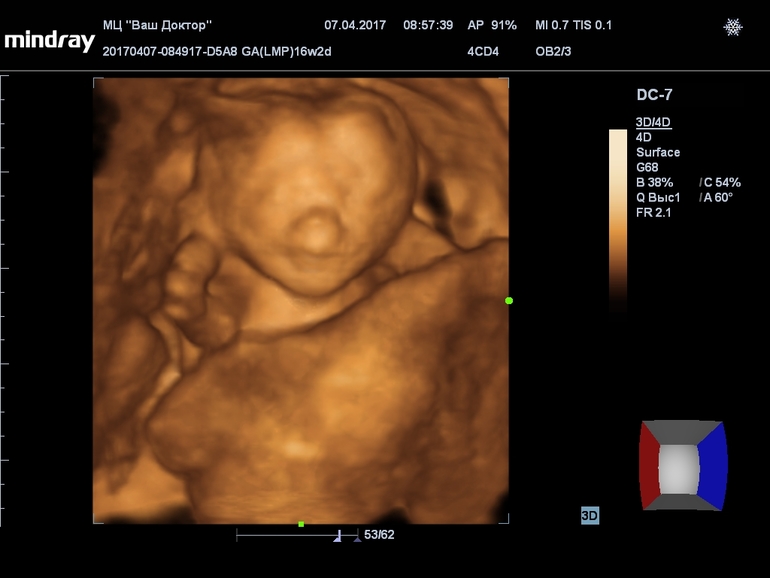

вот наш носик в 16 недель... А в другой клинике с более четким оборудованием, всё замечательно!!!!!!